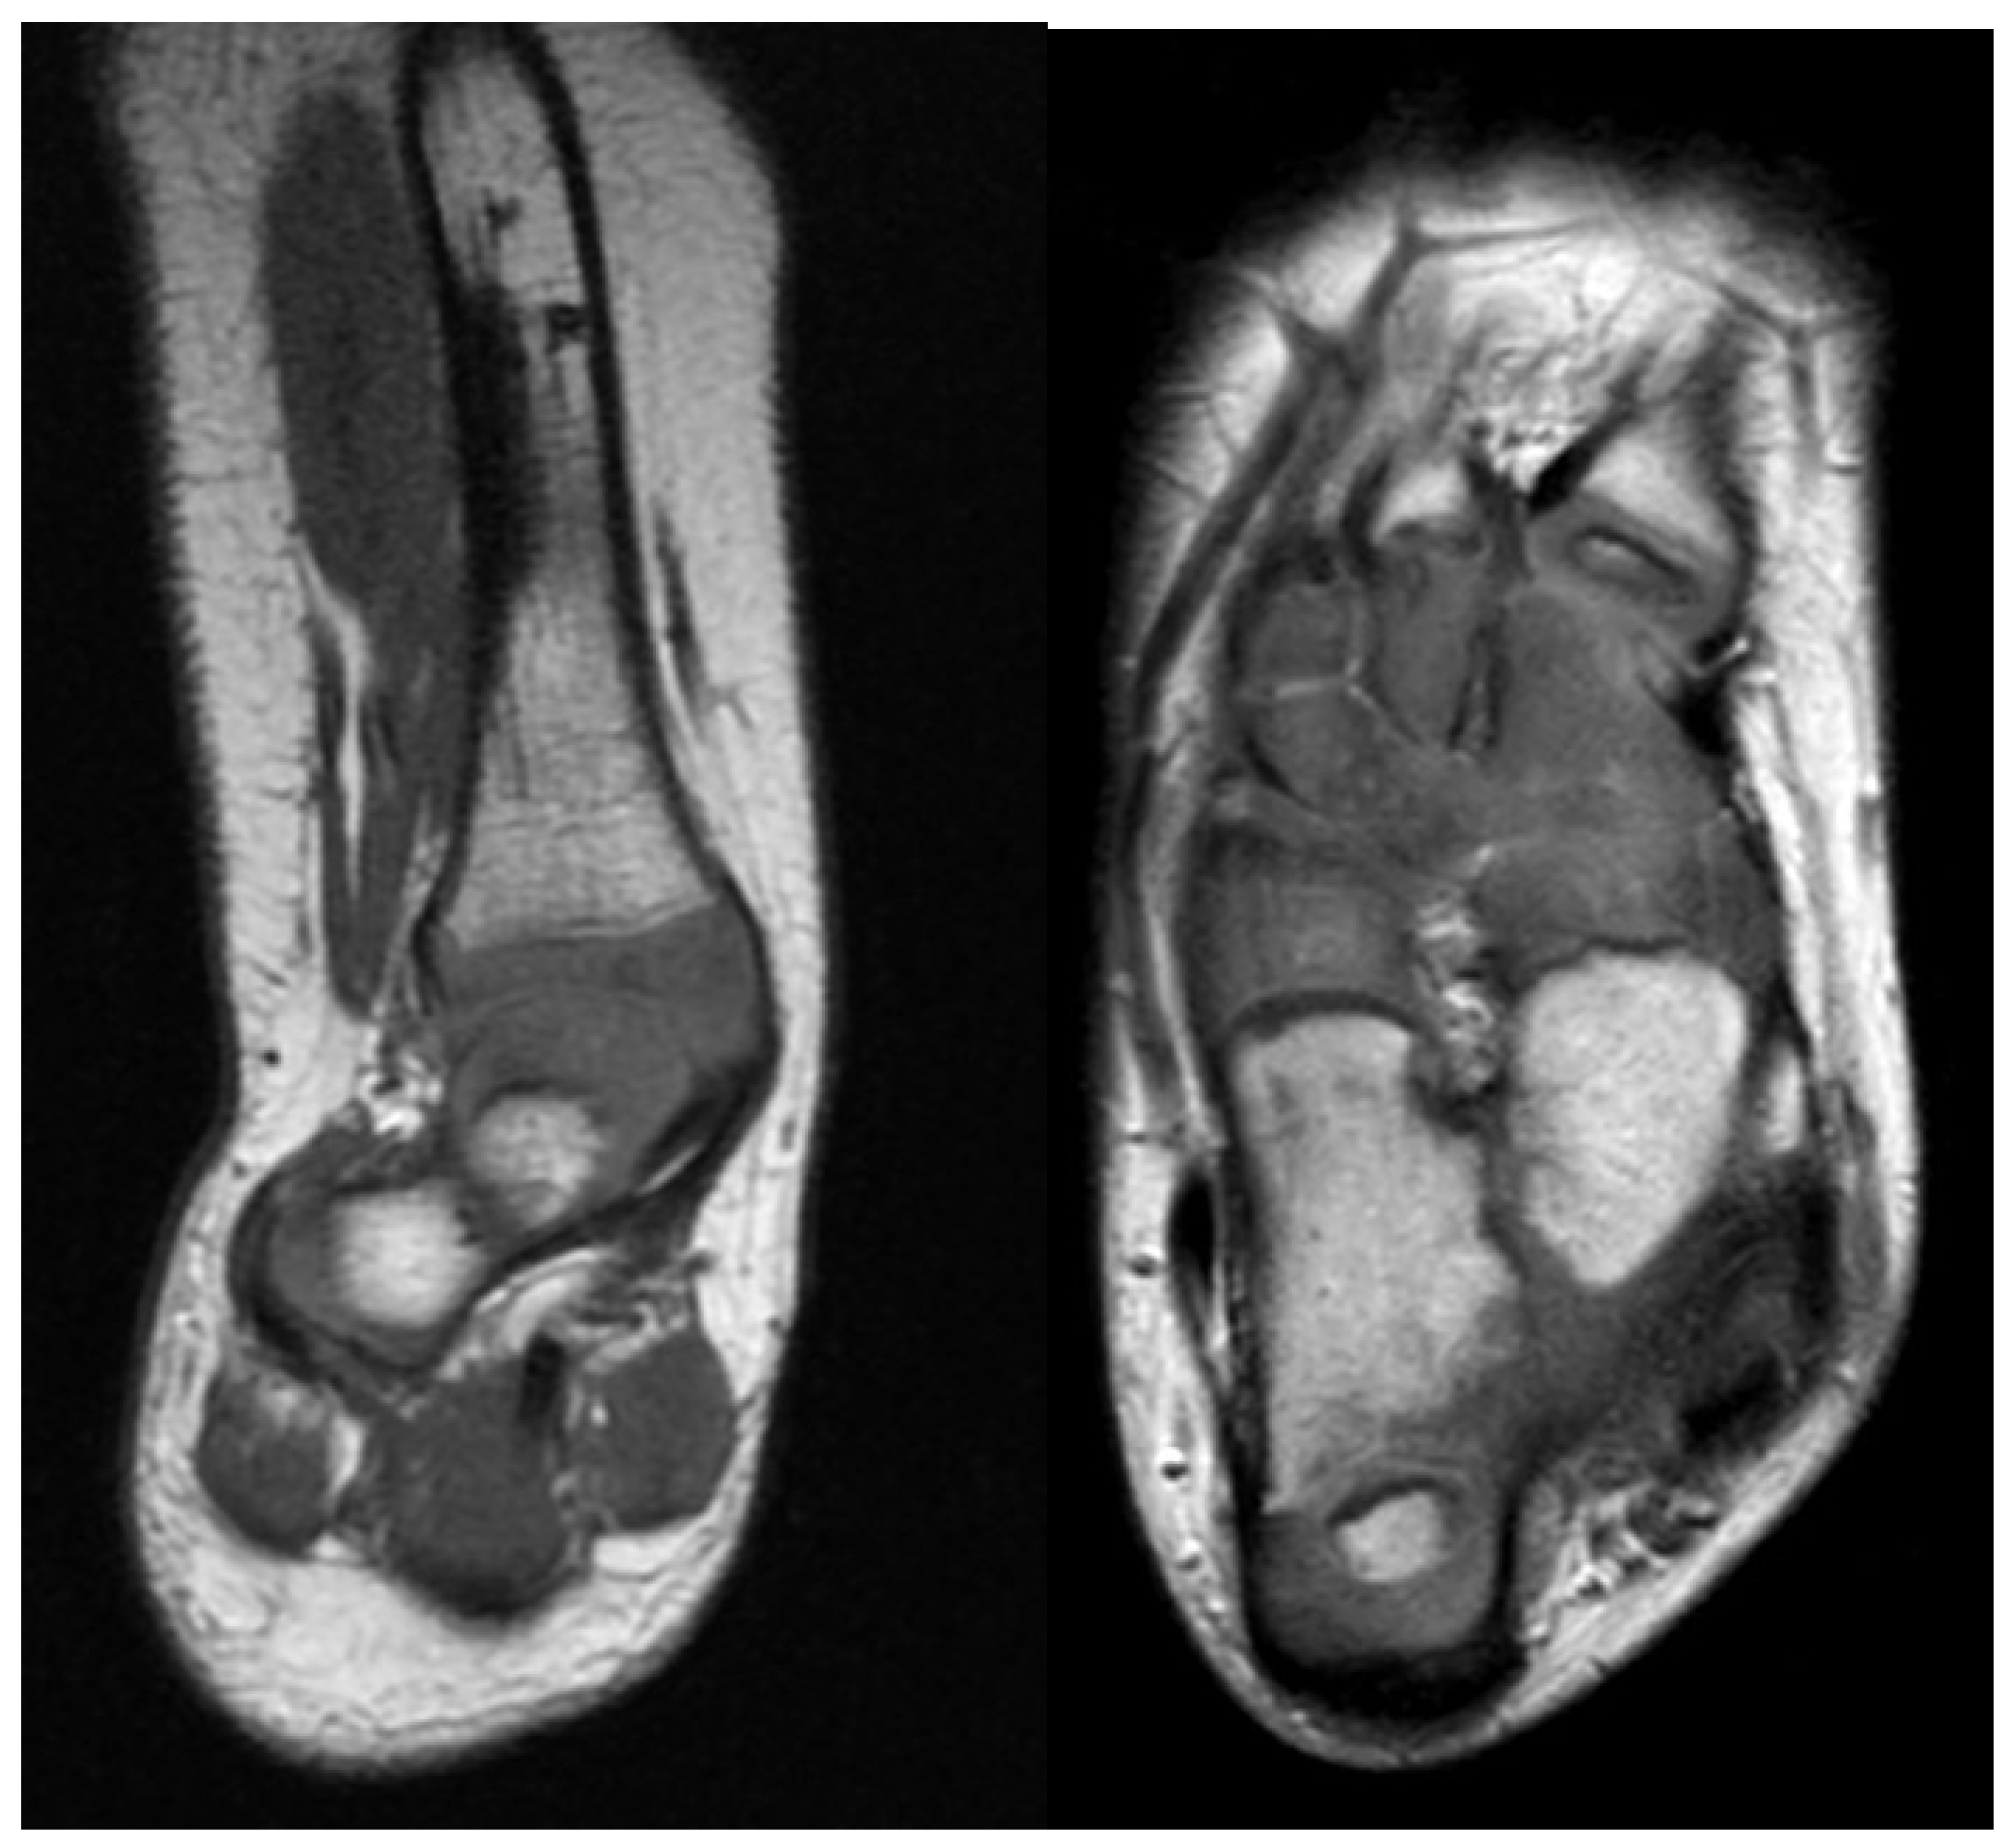

Figure 2.

Left is coronal cut of magnetic resonance imaging (MRI) through the ankle and subtalar regions. This shows a subtalar coalition with the Calcaneus to the side of the talus. The ankle has a ball and socket shape. Right is axial cut of MRI through the foot showing the malunited talo-calcaneal coalition with the calcaneus to the side of the talus. The talonavicular and calcaneocuboid coalitions are also seen.